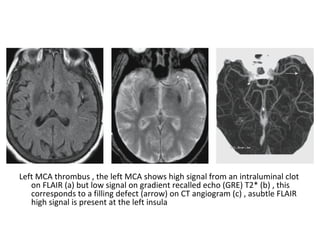

Left MCA thrombus , the left MCA shows high signal from an intraluminal clot

on FLAIR (a) but low signal on gradient recalled echo (GRE) T2* (b) , this

corresponds to a filling defect (arrow) on CT angiogram (c) , asubtle FLAIR

high signal is present at the left insula